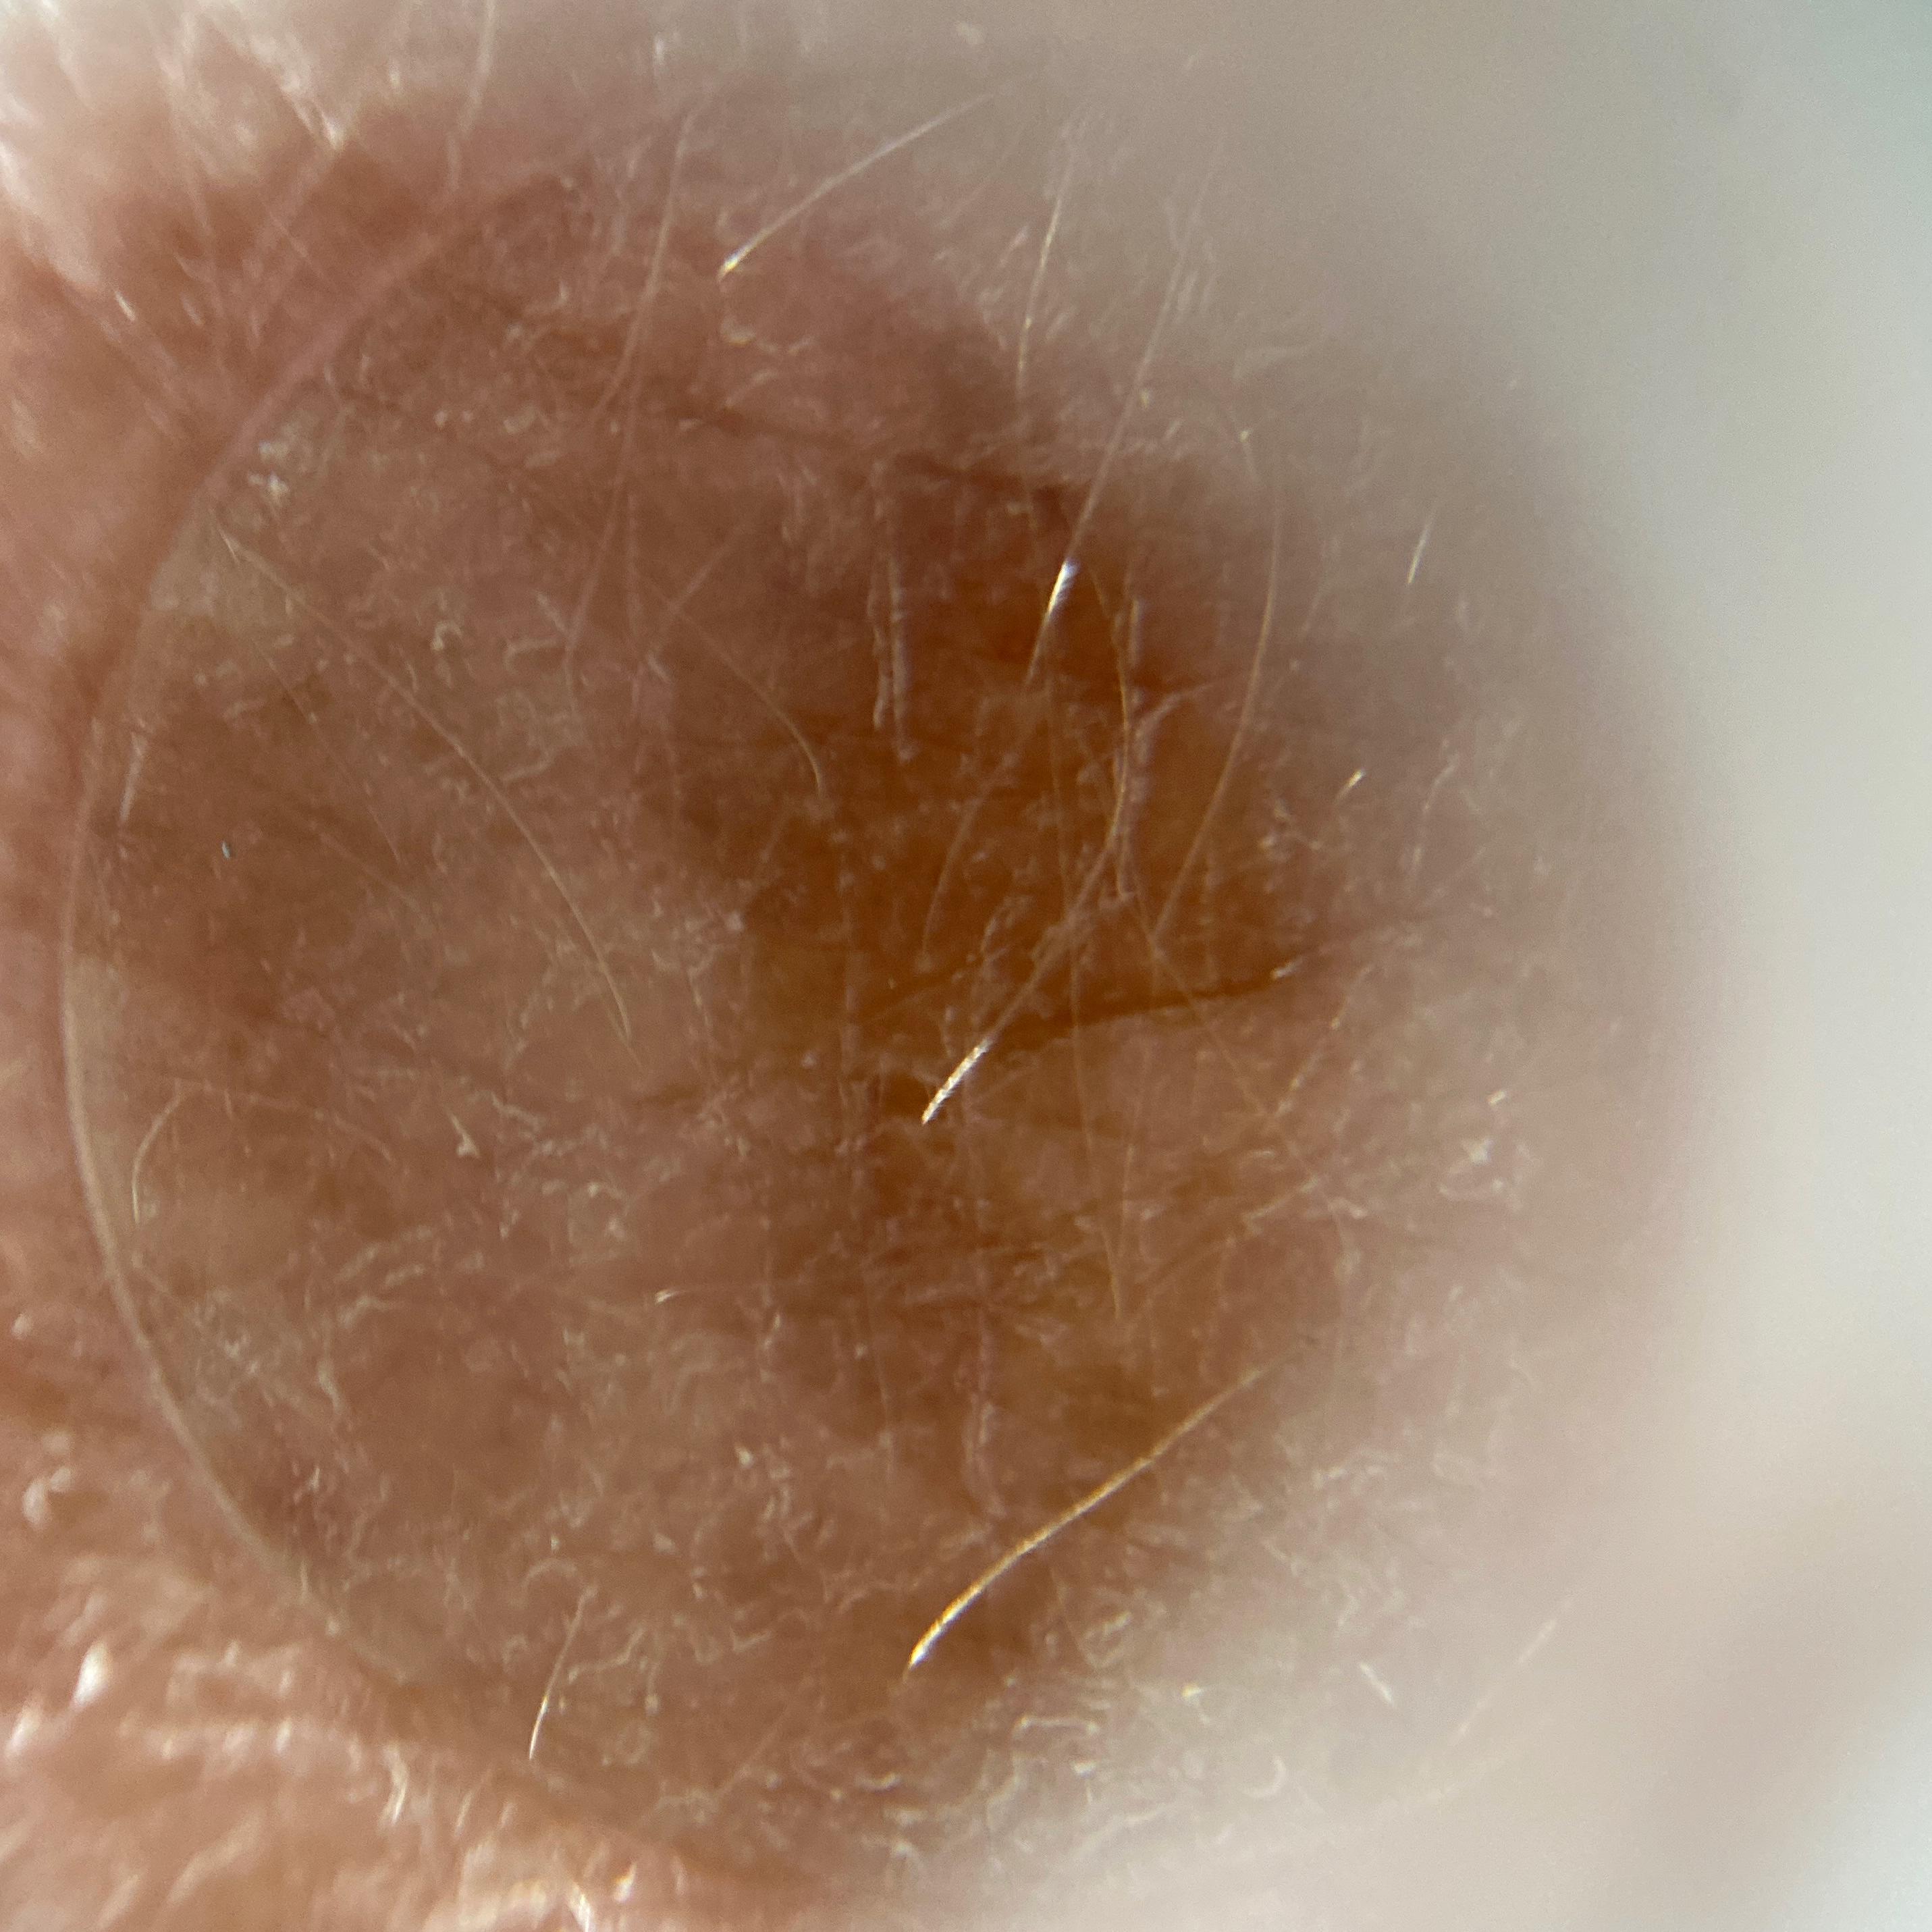

ISIC_5873799

diagnosis_1 Benign

diagnosis_confirm_type single image expert consensus

image_type dermoscopic